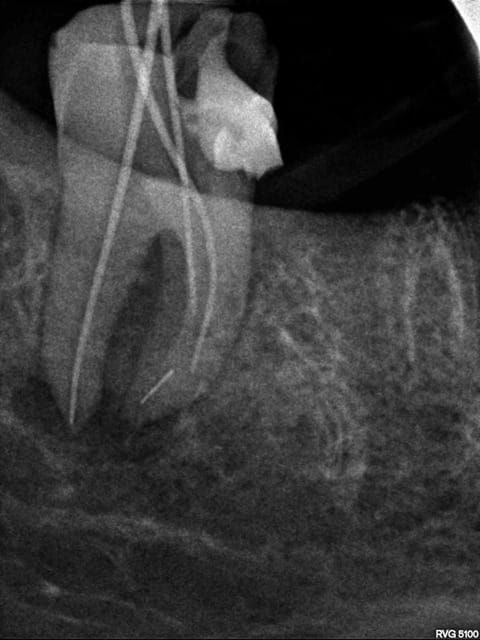

Voila mes deux perles, je me doute bien que l'infection sur la 46 a peu de chance de disparaitre, mais on remarquera sur la 13 la belle continuité de l'instrument sur le gutta qui cache bien son jeu! :-))

Sur ta 46, le pronostic est assez mauvais. Il y a plus d'espoir avec la prémolaire.

pour moi, toutes les dents qui sont représentées sur tes radios sont à extraire maintenant en raison d'une lésion préexistante. Tu as trop de portion de canal non instrumenté pur que tabalanceoit en faveur de la recnstruction osseuse. La molaire était foutue avant l'endo selon moi. ta canine, tu peux eventuellement tenter une resection apicale, mais bon...